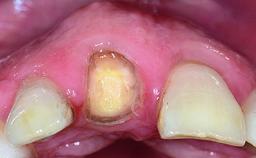

A 15-year-old male patient was referred to us by his pediatric dentist in June 2004 for evaluation of treatment options for his failing tooth 21. The patient had recently seen an endodontist for internal bleaching and been advised that there had been significant resorption and ankylosis. The patient’s mother was concerned because the tooth appeared shorter than the adjacent one. His past dental history was significant for trauma (September 2001), where the tooth had been avulsed and reimplanted. Teeth 11 and 21 had been endodontically treated.

| Bone Volume | Deficient horizontally, requiring prior grafting |